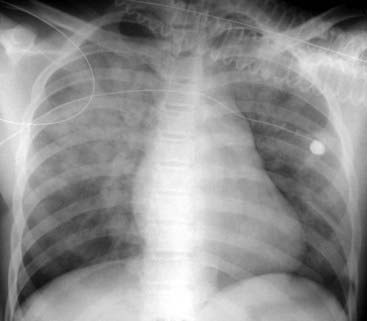

Figure 3-6 Acute pulmonary alveolar edema.

Fluffy, bilateral, perihilar airspace disease with indistinct margins, sometimes described as having a bat-wing or angel-wing configuration, is present (solid white arrows). No air bronchograms are seen. The heart is enlarged. This represents pulmonary alveolar edema secondary to congestive heart failure.